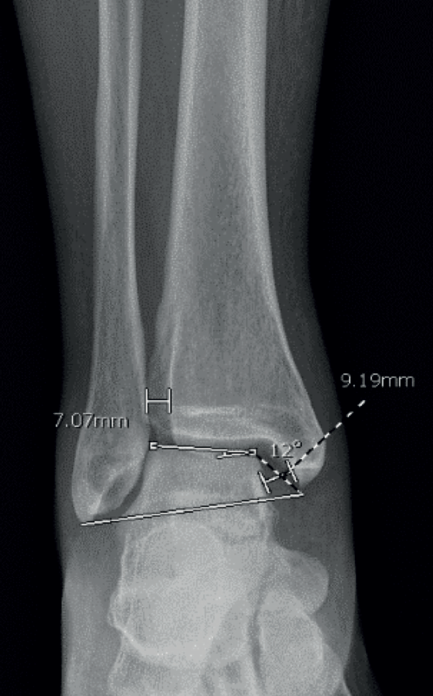

Realizamos las siguientes mediciones radiológicas en la proyección de mortaja del tobillo (rotación interna de 20°) antes de la cirugía, en el tobillo afectado y en el sano, y al final del seguimiento (Figura 3):

- Espacio claro medial (ECM).

- Espacio claro tibiofibular (ECTF).

- Ángulo cruromaleolar (ACM).

Todas las mediciones fueron llevadas a cabo por un único examinador, el becario del equipo, entrenado en cirugía de tobillo y pie. Se utilizó un programa computarizado (Synapse® Picture Archiving and Communication System). Todas las imágenes fueron digitales. Se midió el ECM y el ECTF en mm y el ACM en grados, siendo sus valores normales(19):

- ECM ≤ 4 mm.

- ECTF < 6 mm.

- ACM = 12 a 14°.

Se registró el promedio en mm de la medición del ECM y el ECTF, y en grados del ACM, en el tobillo sano y en el tobillo fracturado antes de la cirugía y al final del seguimiento.

El ACM promedio en el tobillo sano fue de 12,37°, en el fracturado de 10,68° y en el postoperatorio de 12,16° (Figura 4).